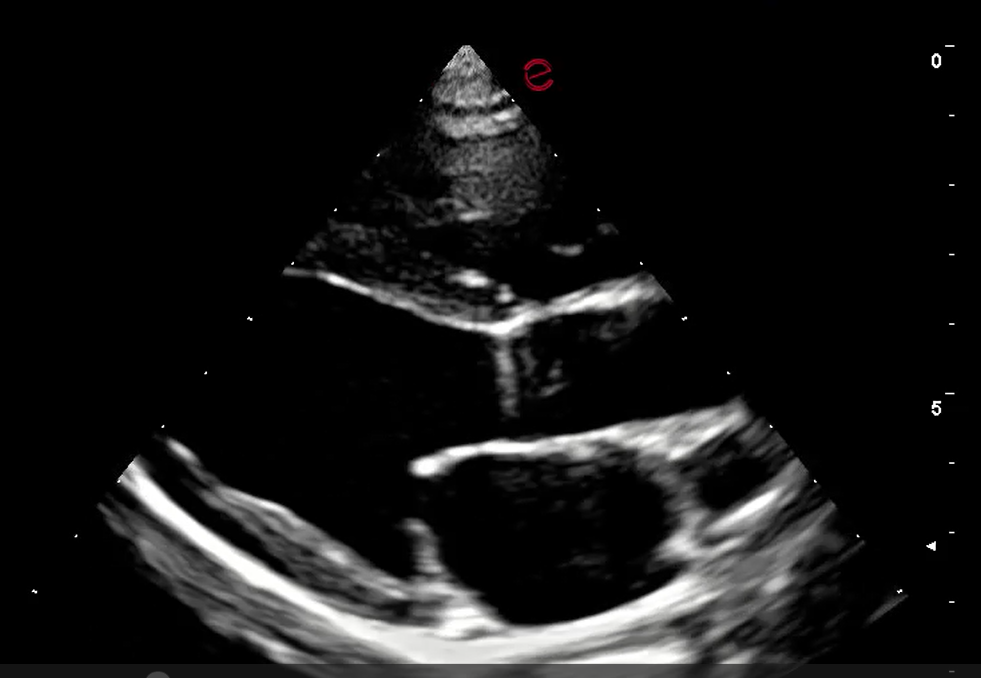

• New or worsening heart murmur?

Are medications indicated yet?

Is it safe for this pet to undergo anesthesia for a dental cleaning?

An echocardiogram can answer these questions and more. And, you will have a cardiologist on your team for making clinical decisions.